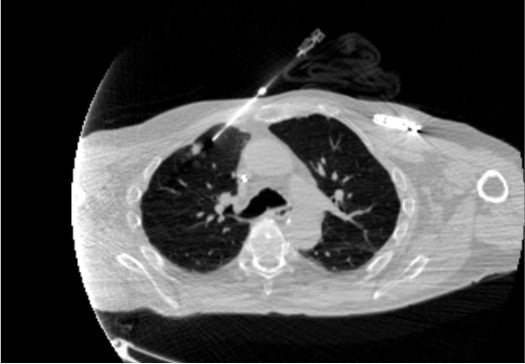

View expected pulmonary hemorrhage

CT showing expected pulmonary hemorrhage after lung biopsy